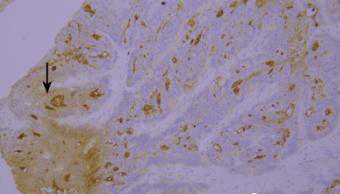

7.干片

干片导致的假阴性(黑色箭头区域)。

优化建议:

加入Tween-20的缓冲液能够更好地防止切片干燥。

8.边缘效应

边缘效应造成的非特异性染色(黑色箭头区域)。

组织切片与玻片黏贴牢固,试剂完全覆盖组织防止干片,加入Tween-20的缓冲液能够更好地防止边缘效应。